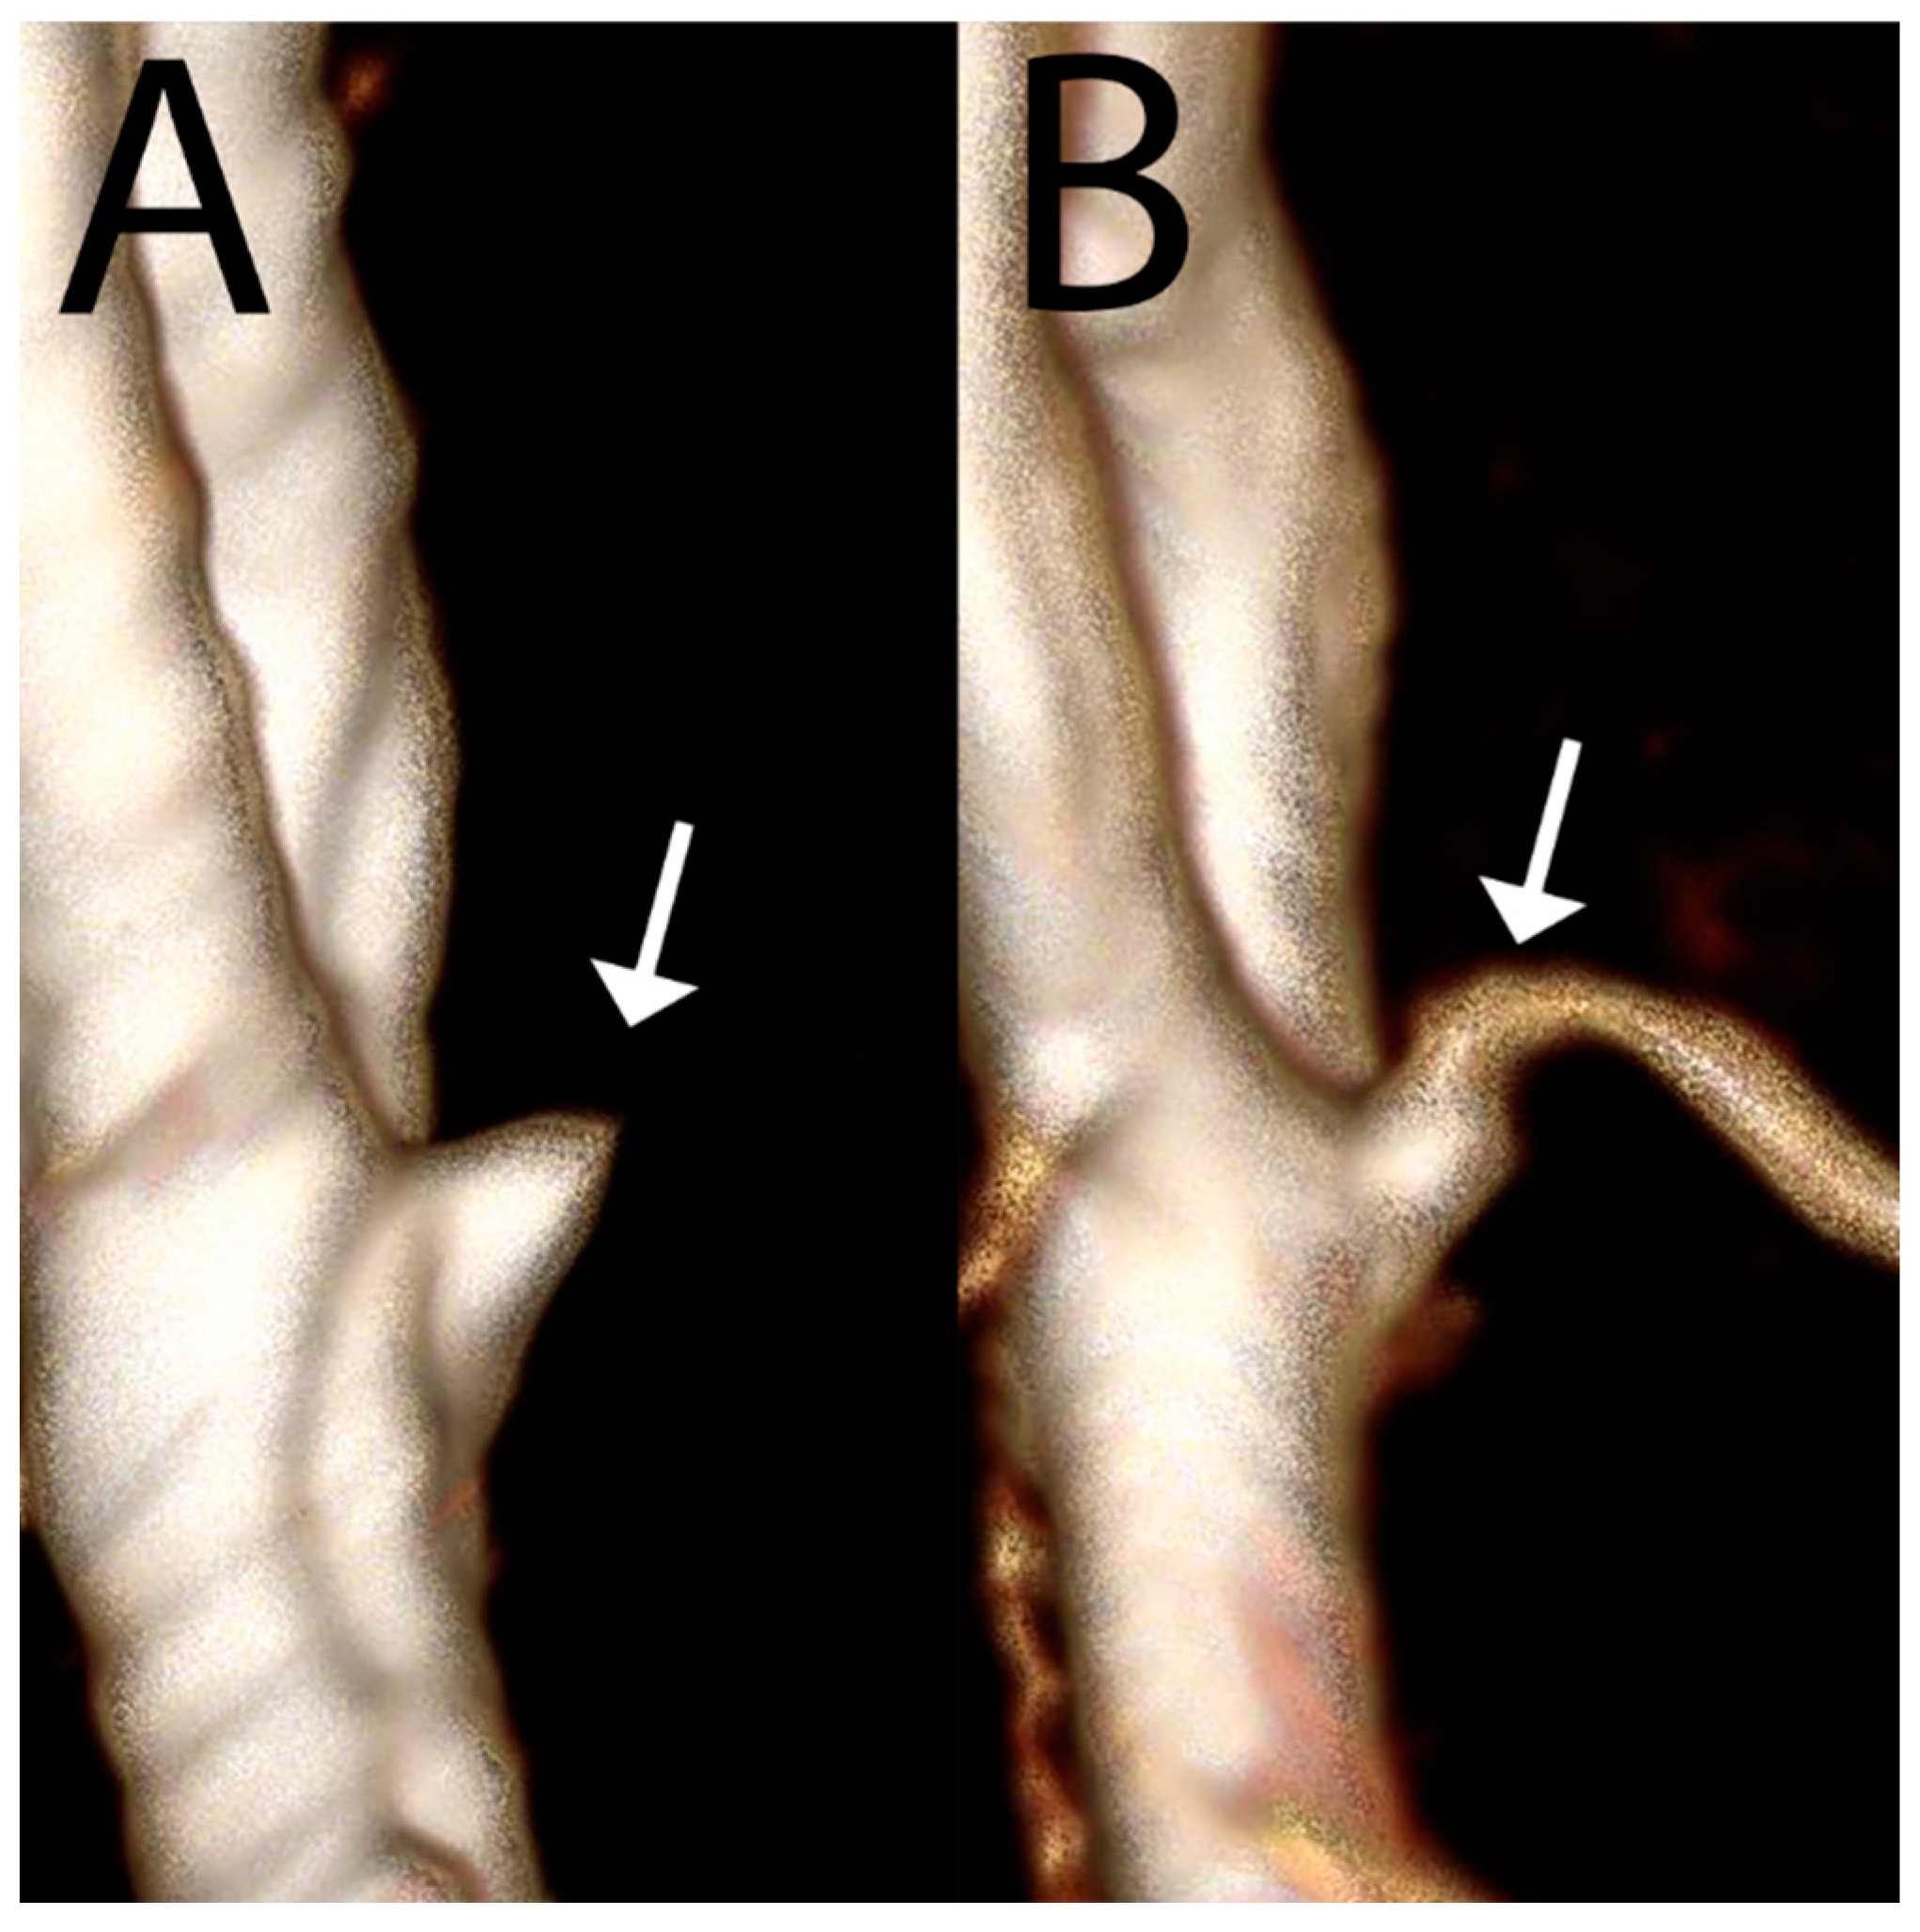

- Wermer, M.J.; van Walderveen, M.A.; Garpebring, A.; van Osch, M.J.; Versluis, M.J. 7 Tesla MRA for the differentiation between intracranial aneurysms and infundibula. Magn. Reson. Imaging 2017, 37, 16–20. [Google Scholar] [CrossRef] [PubMed]